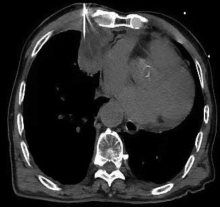

目的比较CT与超声引导下经皮肺或胸膜病变穿刺活检的有效性和安全性。方法回顾性分析2017年2月至2020年10月在湖北医药学院附属十堰市人民医院接受CT或超声引导下经皮穿刺的病灶靠近胸膜的193例肺占位患者的临床资料。根据穿刺方式将患者分为CT引导组(n=115)和超声引导组(n=78)。比较两组患者的一般临床资料、病理检查结果及穿刺成功率、并发症发生率。采用logistic回归进行单因素、多因素分析。结果CT引导组恶性肿瘤检出率(60.00%,69/115)高于超声引导组(50.00%,39/78),但差异无统计学意义(χ2=1.89,P=0.170)。CT引导组穿刺成功率(88.70%,102/115)略低于超声引导组(93.59%,73/78),差异无统计学意义(χ2=1.32,P=0.251)。CT引导组术后并发症发生率(18.26%,21/115)高于超声引导组(6.41%,5/78),差异有统计学意义(χ2=5.60,P=0.018);CT引导组气胸发生率(13.04%,15/115)高于超声引导组(3.85%,3/78),差异有统计学意义(χ2=4.65,P=0.031);CT引导组出血发生率(5.22%,6/115)高于超声引导组(2.56%,2/78),差异无统计学意义(χ2=0.82,P=0.364)。CT引导组中有1例(0.87%)患者出现严重出血需要手术治疗,5例(4.35%)需要胸腔闭式引流进行治疗,超声引导组中未出现气胸或出血需要进行引流或手术治疗患者。单因素分析发现穿刺方法为影响病变-胸膜接触弧长(LPCAL)≥38 mm的患者穿刺成功率的独立危险因素(OR=7.82,95%CI为1.57~35.50,P=0.039);多因素分析显示穿刺方法为影响LPCAL≥38 mm患者穿刺成功率的独立危险因素(OR=7.75,95%CI为1.44~41.36,P=0.042)。LPCAL≥38 mm患者中,CT和超声引导穿刺成功率分别为84.38%(54/64)、98.00%(49/50),CT引导穿刺成功率低于超声引导,差异具有统计学意义(χ2=4.52,P=0.034);LPCAL<38 mm患者中,CT和超声引导穿刺成功率分别为94.12%(48/51)、85.71%(24/28),CT引导的穿刺成功率高于超声引导,但差异无统计学意义(χ2=0.71,P=0.399)。结论超声引导下经皮肺或胸膜病变穿刺活检具有诊断正确率高、并发症少等优点,其与CT引导下穿刺活检均为胸壁病变穿刺的可行方法。当LPCAL≥38 mm时,超声引导下穿刺活检可能更具优势。

Song Tongjun, Deng Rui, Fei Lei, Lei Jinhua, Cao Fengjun. Comparison of the efficacy and safety of percutaneous needle biopsy of pulmonary or pleural lesions guided by CT and ultrasound[J]. Journal of International Oncology, 2022, 49(9): 526-531.